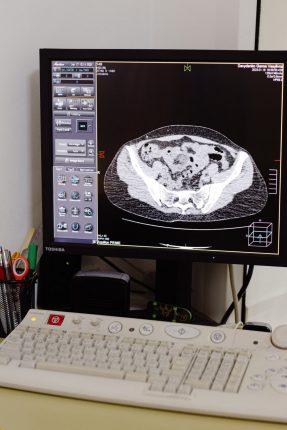

Якісну діагностику для лікування хворих з патологією хребта, суглобів та опорно-рухового апарату здійснюють в Івано-Франківській центральній міській клінічній лікарні за допомогою функціональної рентгенографії.

Перевага такої діагностики полягає в тому, що лікар-рентгенолог ЦМКЛ бачить об’єм і функцію, як себе «поводить» той чи інший суглоб, коли він повністю розігнутий чи зігнутий і коли знаходиться у звичайному стані. За допомогою функціональної рентгенографії можна виявити приховану патологію, якої не видно під час статичного рентген-обстеження.

«Рентгеном ми можемо довести, що функція якогось органу, кінцівки чи з’єднання кісток має хворобу не тільки тоді, коли перебуває в нерухомому стані, але й коли рухається. Або, бувають випадки, що під час рентгенівського знімку в нерухомому стані, орган можна діагностувати як здоровий, але, якщо дослідити його функцію в момент роботи, то вона є порушена», – пояснює завідувач рентгенологічного відділення ЦМКЛ Ігор Соколовський.